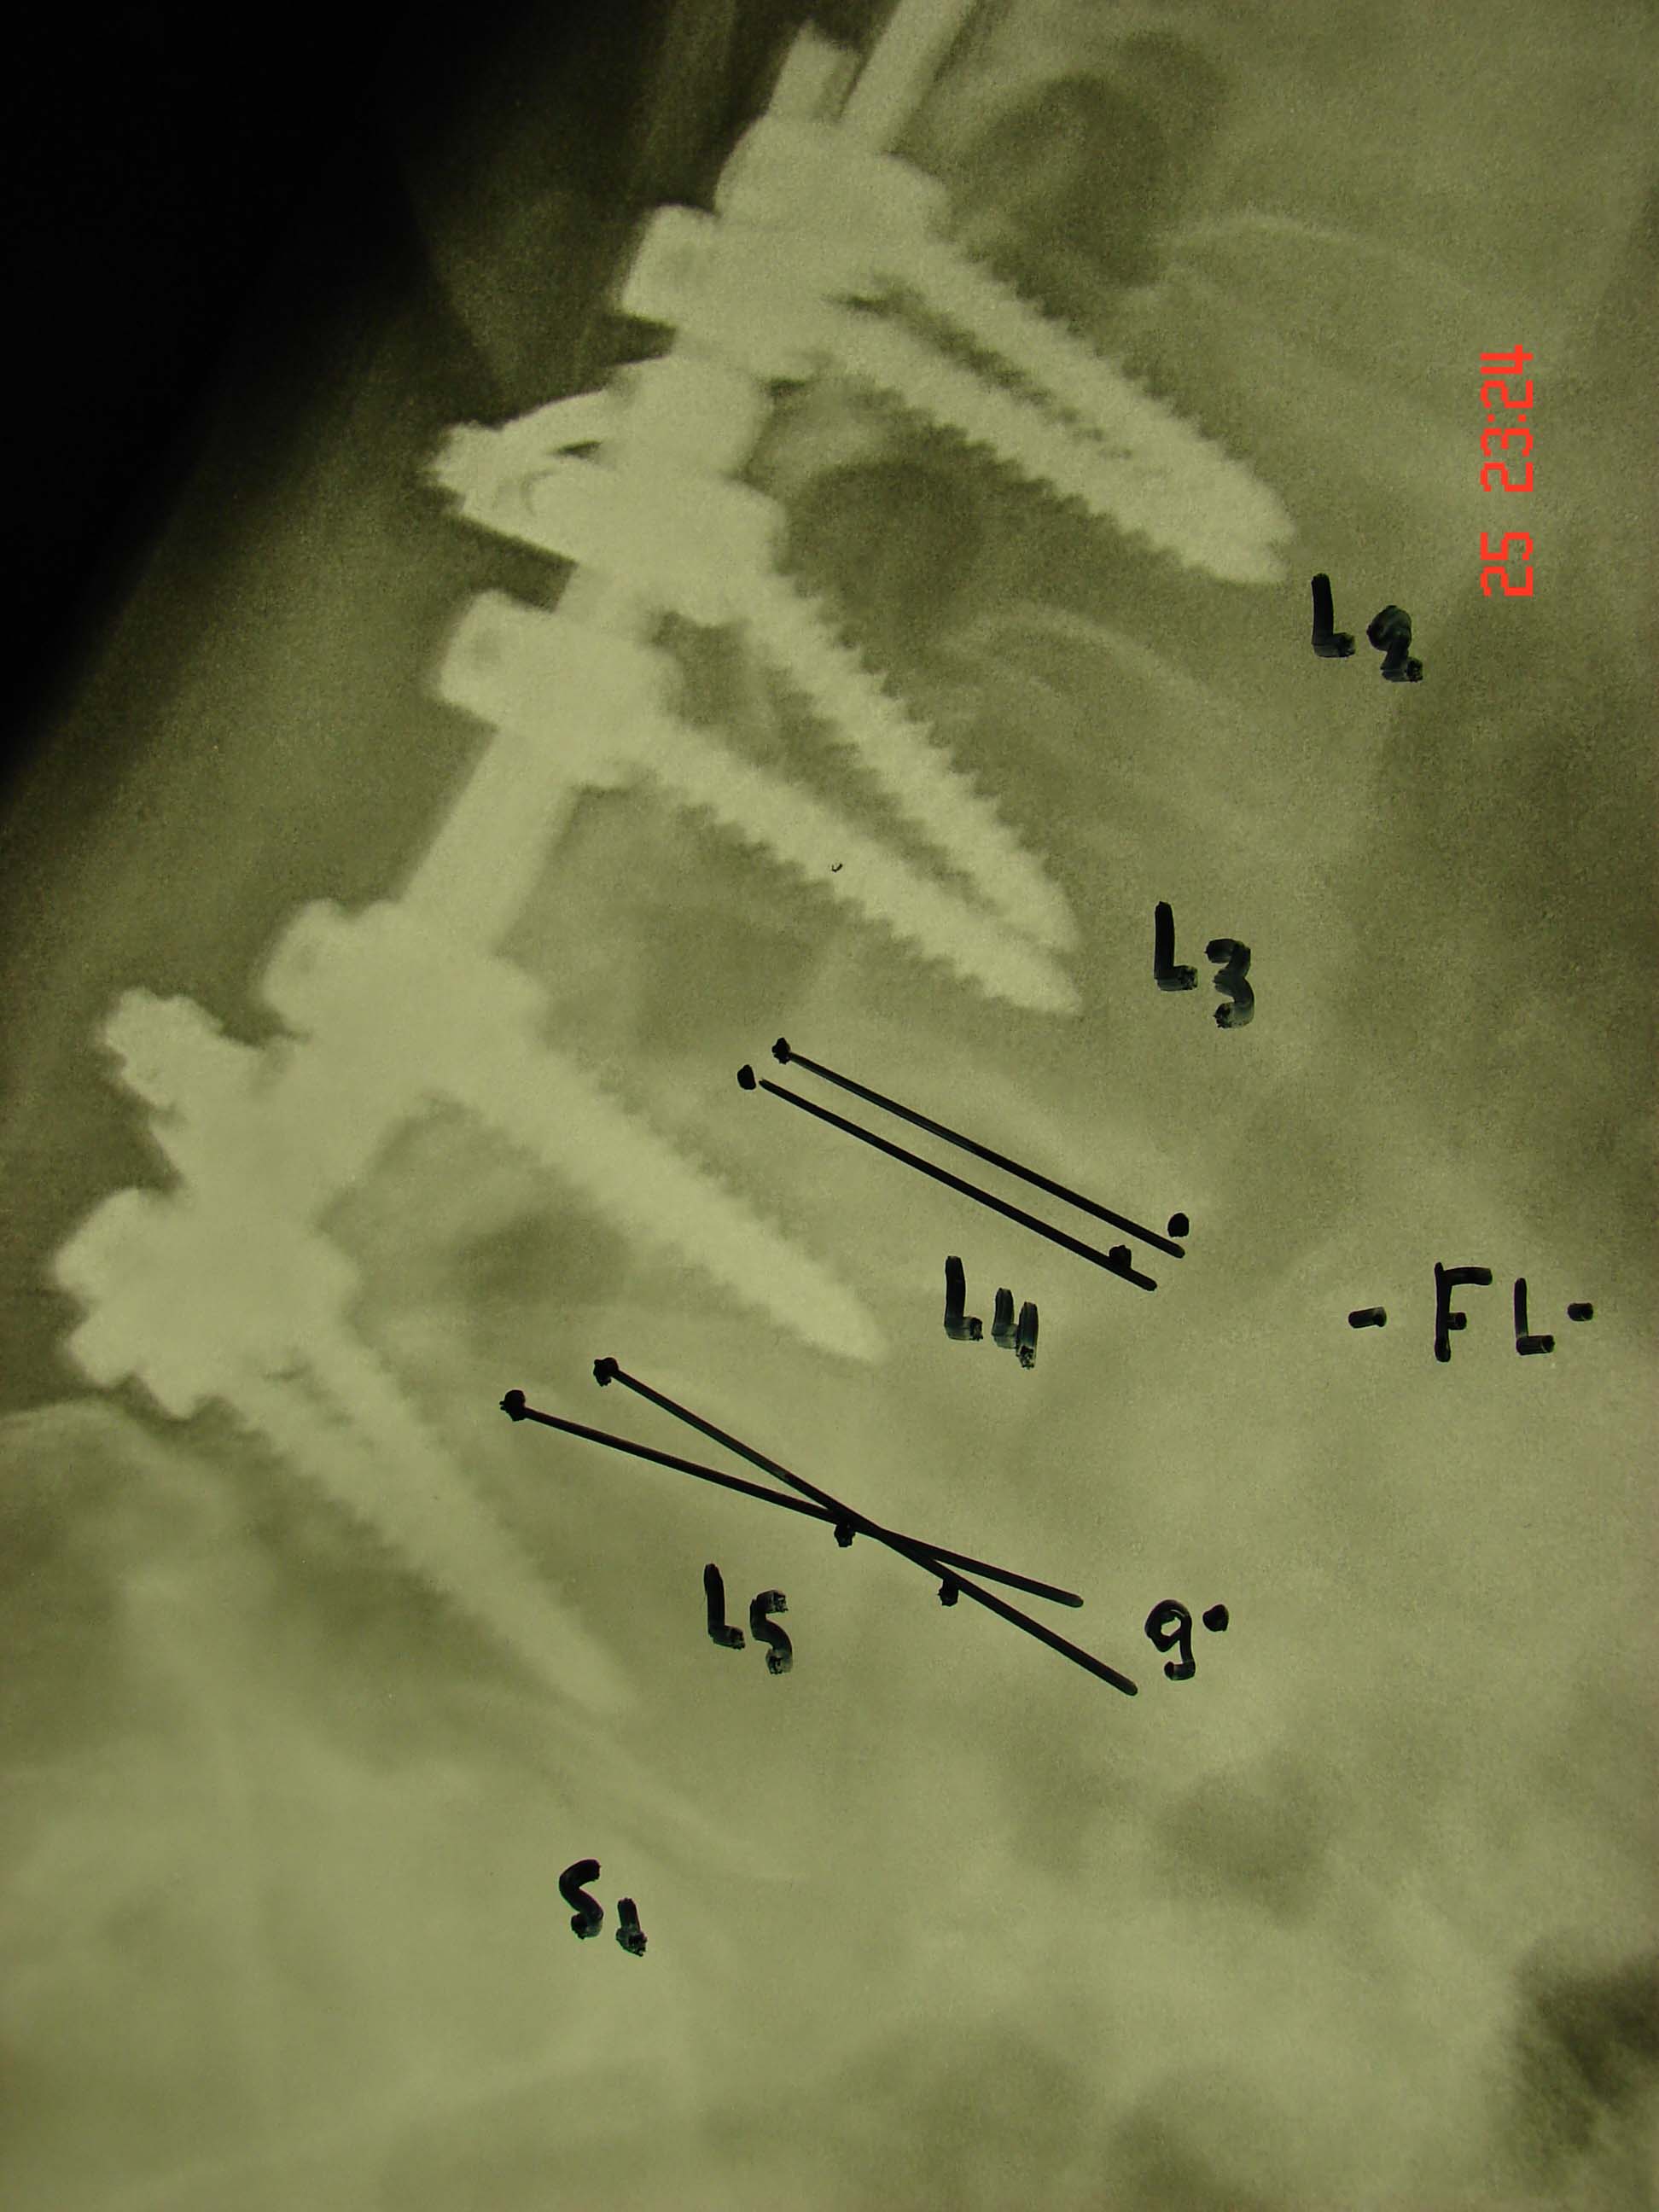

Εικόνα 6 (α,β)  Δια την αντιμετώπιση της αστάθειας στο επίπεδο Ο4-Ο5, πραγματοποιείται αναθεώρηση της σπονδυλοδεσίας και επέκταση μέχρι το ιερό οστούν και τοποθετούνται μεσοσπονδύλια εμφυτεύματα στα επίπεδα Ο3-Ο4, Ο4-Ο5, Ο5-Ι1 με την τεχνική TLIF.

Eικόνα 7 (α,β) Μετεγχειρητικές ακτινογραφίες 12 μήνες μετά τη χειρουργική επέμβαση (Revision)  Διατηρείται η καλή θέση της Σπονδυλικής Στήλης και των υλικών της σπονδυλοδεσίας.

Η αστάθεια αποδίδεται στην απώλεια στήριξης του κοχλιών που είχαν μπεί στο σώμα του 5ου οσφυϊκού σπονδύλου, λόγω της υφιστάμενης προχωρημένης οστεοπενίας. Αυτό κατέστησε αναγκαία την επέκταση της σπονδυλοδεσίας μέχρι τον 1ο ιερό και τη τοποθέτηση μεσοσπονδυλίων εμφυτευμάτων στα επίπεδα Ο3-Ο4, 04-Ο5, 05-Ι1. Με αυτό τον τρόπο εξασφαλίσθηκε η σταθερότητα στην περιοχή της σπονδυλοδεσίας.